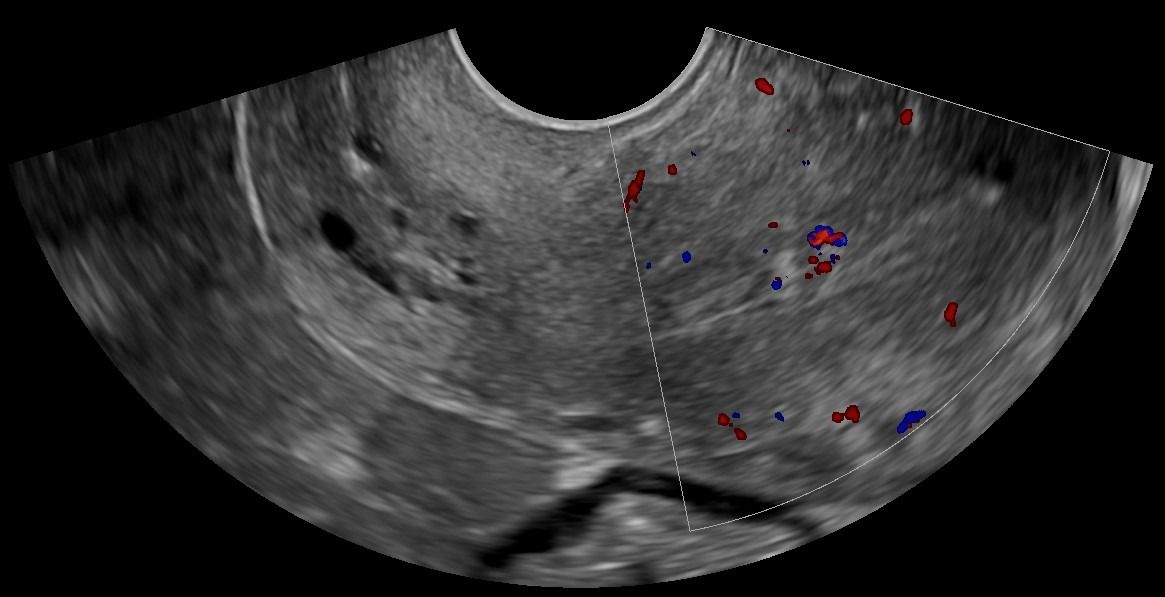

- Ωοθήκες: Η απεικόνιση των ωοθηκών περιλαμβάνει την αξιολόγηση του μεγέθους, της μορφολογίας και της υφής τους. Με το Διακολπικό Υπερηχογράφημα, μπορούν να μετρηθούν τα ωοθυλάκια και να διερευνηθεί η παρουσία συνδρόμου πολυκυστικών ωοθηκών. Οι εστιακές βλάβες στις ωοθήκες, συμπαγείς ή κυστικές, μπορούν να αξιολογηθούν ως καλοήθεις ή ύποπτες, με τη βοήθεια του Έγχρωμου Doppler για την απεικόνιση της αγγείωσης και της ροής του αίματος.